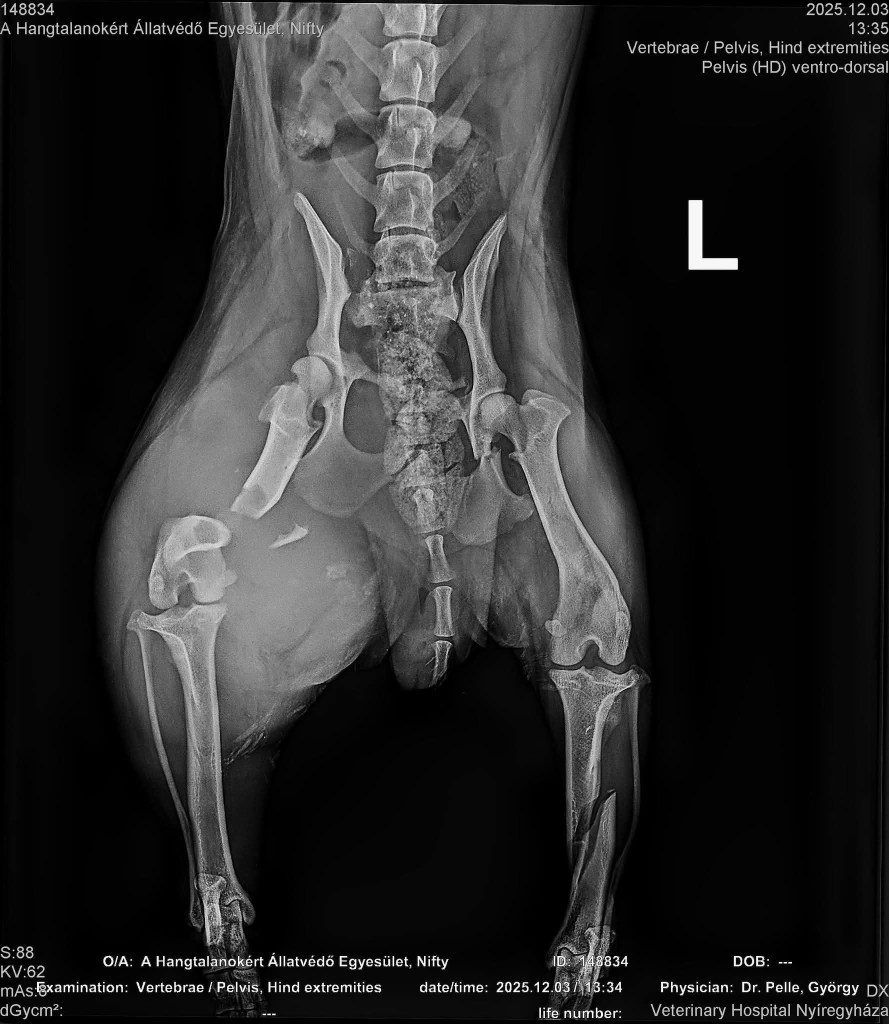

Den Röntgenbildern ist zu entnehmen, dass mehrere Brüdhe (Schienbein, Oberschenkelknochen, angebrochenes Becken) behoben wurden. Stunden vergingen, doch die tapfere Mausi hat sich gut geschlagen. ![]()